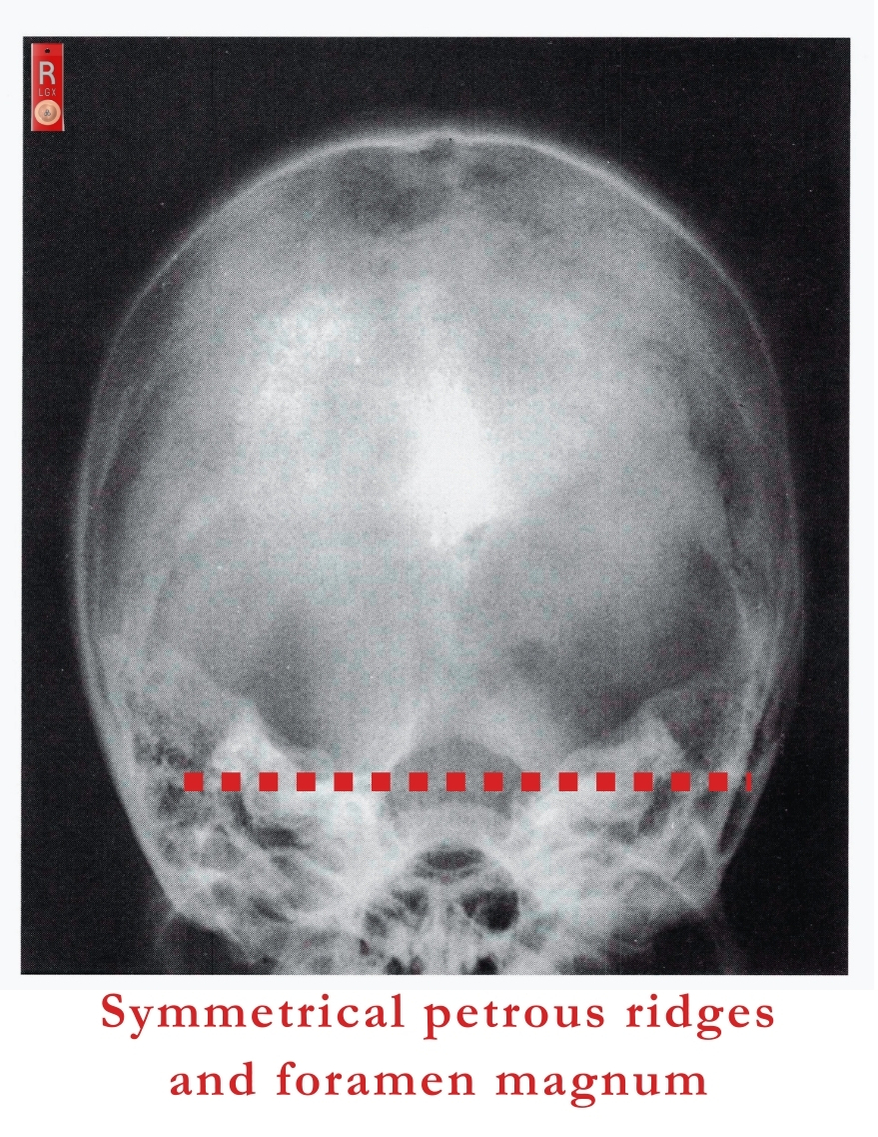

Image Evaluation Criteria

- The petrous ridges and foramen magnum should be symmetrical, indicating no rotation.

- The dorsum sellae must appear centered and visualized within the foramen magnum.

- The entire skull should be visible, especially the vertex, without any cut-off, rotation or distortion.